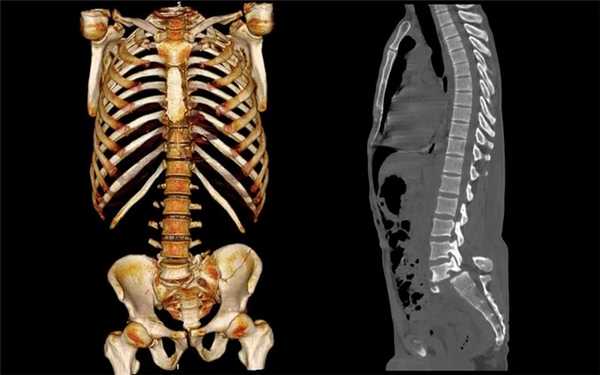

Диагностировать опухолевые образования в позвонках лучше всего с помощью КТ позвоночника или МРТ позвоночника с контрастом.

Диагностику опухолевых заболеваний спинного мозга и позвонков чаще всего проводят при помощи КТ позвоночника или МРТ позвоночника с контрастом. Чтобы выяснить, какой из методов лучше справится с этой задачей, необходимо разобраться в механизме действия каждого из методов.

Компьютерная томография - это рентгенологический вид диагностики. Она дает прекрасную возможность определить новообразование в костных структурах даже на ранних стадиях развития. Однако на КТ визуально сложно разделить патологическую и здоровую ткань в спинном мозге. Для этих целей пациенту проводят процедуру КТ-миелографии с введением контрастного вещества. Использование йодосодержащего контраста не всегда приемлемо. У некоторых пациентов может быть аллергия на состав или серьезная болезнь почек, при которых контраст не применяют. Не стоит забывать и о лучевой нагрузке. В среднем при КТ всего позвоночника пациент получит дозу облучения, равную 5-8 мЗв. Поэтому при диагностике объёмных образований спинного мозга и оболочек приоритетным методом обследования будет МРТ позвоночника с программой миелография.

Магнитно-резонансный томограф лучше визуализирует мягкие и мозговые ткани и позволяет дифференцировать здоровую ткань и ткань патологическую. МРТ при опухоли поможет определить место очага, вид злокачественного новообразования и степень инвазии в соседние ткани. Кроме того, при МР-томографии не используются вредные рентгеновские лучи, и потому диагностику можно проводить неограниченное количество раз беременным женщинам и детям.

Компьютерная томография показывает состояние позвонков и их отростков, межпозвоночных дисков, связок. Обследование позвоночника с помощью КТ проводят перед и после операций, для контроля диагностических процедур по забору материала на исследование. Томография позволяет оценивать плотность позвонков и прогнозировать компрессионный перелом.

Обследование КТ помогает обнаружить такие патологии позвоночника:

Позвонковая ткань отличается высоким естественным контрастом на КТ. Поэтому обследовать повреждения позвонков рекомендуется с помощью МСКТ.

На безконтрастных КТ большая часть экстрамедуллярных и интрамедуллярных внутриканальных новообразований не отличается от спинного мозга. Если контрастное вещество было введено болюсным способом, то необходимо качественно контрастироваться станут лишь богато васкуляризированные новообразования - пороки развития сосудов, гемангиобласты, ангиомы. Используя компьютерную томографию, также можно определять внутримозговые кисты и сирингомиелию на простых срезах в шейной области.

Поэтому при подозрениях на патологии спинномозгового канала, предпочтительным вариантом считается магнитно-резонансная томография. При расположенных за пределами спинномозгового канала экстрадуральных новообразованиях применяется МСКТ. К КТ-мелографии (с внутривенным контрастированием) обращаются при условии, что определение опухоли позвоночника на МРТ провести невозможно.